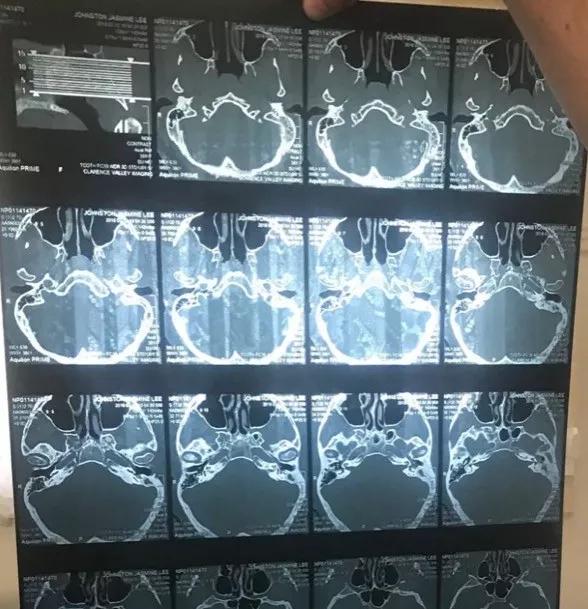

CT扫描显示,Small的耳朵深处已被感染,这里非常靠近她的大脑。

而这一切竟然都是由于棉签上松散棉线引起。

更令人难以置信的是,医生断定,耳朵里的这些小棉块已堆积了长达五年之久!

很快,Small经历了一场大手术,最终保住了性命,但她的左耳已遭到永久性损害,接下来她还需要面临一系列恢复手术,甚至佩戴助听器。

医学团队的CT扫描显示:他的头骨下靠近左耳道的位置有两块充满脓液的肿块,再晚治疗情况就危险了。

终于在脑成像的帮助下他们发现男子的耳道中有一个异物。经过鉴定,导致严重感染的东西是一小撮棉花。